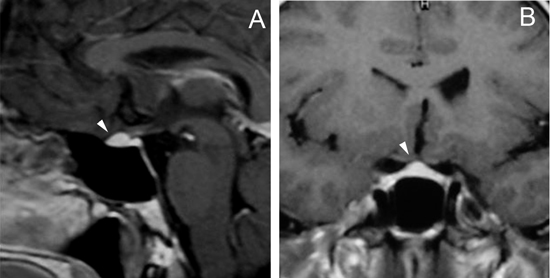

En los tumores grandes (macroadenomas) la TAC puede entregar información diagnóstica adecuada, pero no supera la definición que se logra con equipos de RM superconductores (Figuras 2 A y 2B).

Figura 2A y B. Cortes sagitales de RM y TAC. Adenoma pituitario con invasión del esfenoides y del clivus (puntas de flecha). Es posible demostrar las estructuras óseas en RM con similar precisión que la TAC.